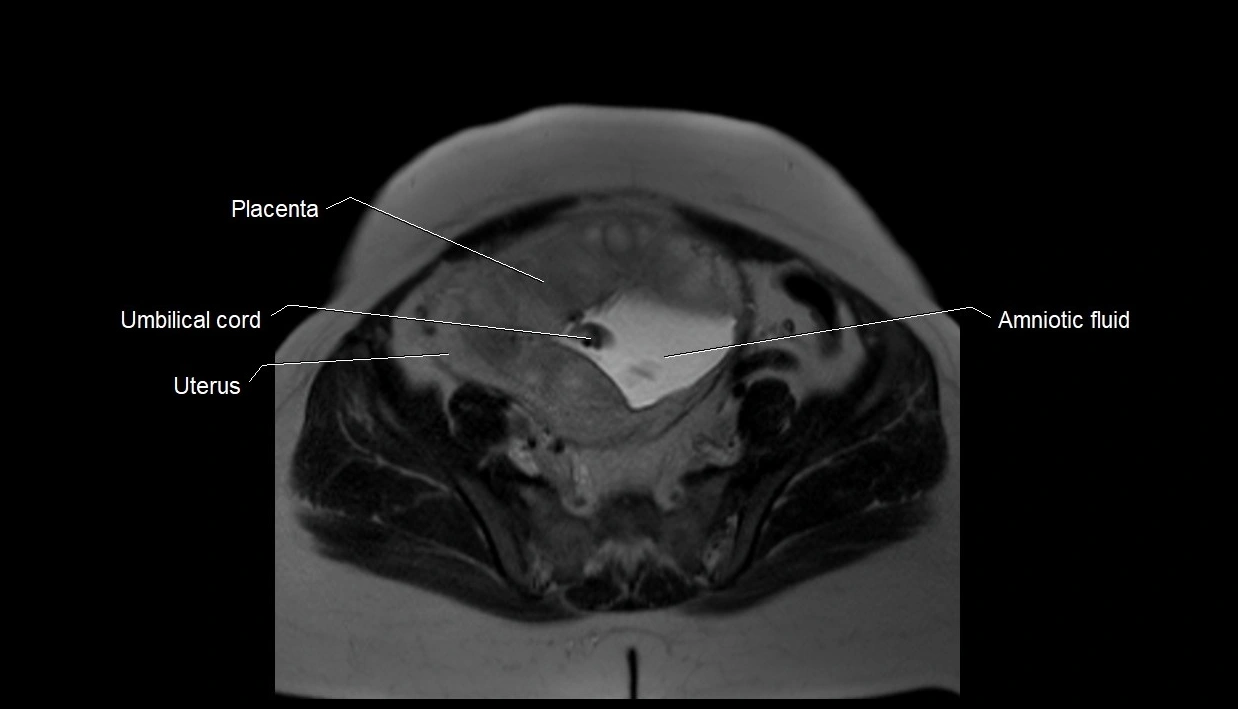

MRI Appearance

T2 HASTE (T2 GRE):

• Amniotic fluid shows very bright hyperintense signal

• Provides natural contrast against fetus and placenta

• Small particles (vernix) may appear as scattered hypointense foci within bright fluid

MRI image

image